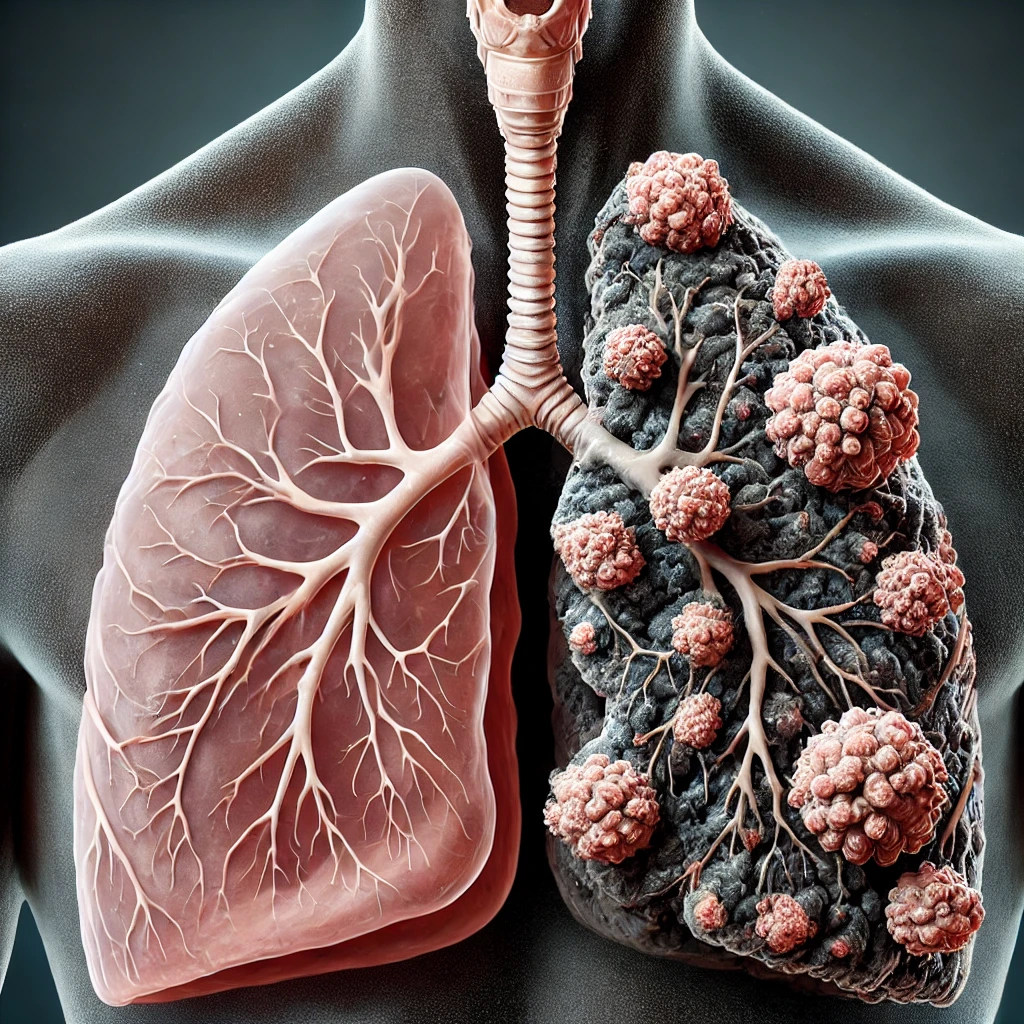

마이코플라즈마(Mycoplasma)는 최근 들어 건강을 위협하는 주요 병원체로 급부상하고 있습니다. 작은 세균 하나가 사람의 폐를 감염시키고, 자칫하면 심각한 폐렴으로 이어질 수 있다는 사실을 알고 계셨나요? 심지어 이 세균은 기존 항생제에도 잘 반응하지 않기 때문에 치료 시점이 늦어지면 고통스럽고 긴 치료가 필요할 수 있습니다.

Q3. 마이코플라즈마 폐렴은 위험한가요?

A: 적절한 치료를 받지 않으면 마이코플라즈마 폐렴은 심각한 합병증을 유발할 수 있습니다. 특히 노인, 소아, 면역력이 약한 사람들에게는 치명적일 수 있으므로, 기침이 오래 지속되거나 열이 동반되는 경우 즉시 병원을 방문해 진단받는 것이 중요합니다.